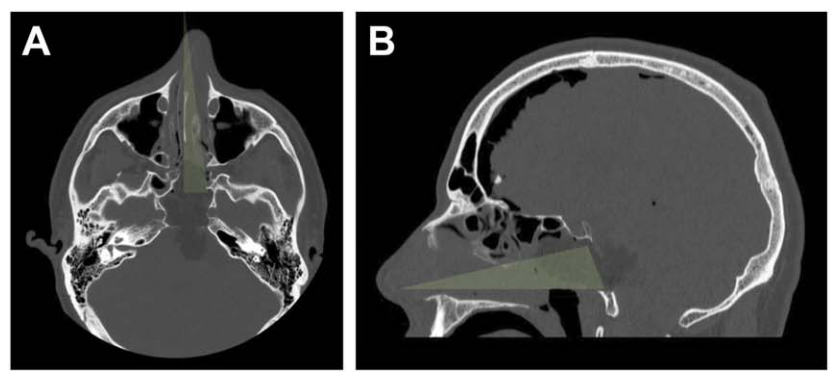

A、B:術后 CT 軸位及矢狀位,綠色顯示單鼻孔入路,鼻腔完整性得以保持;鼻中隔、上頜竇、后組篩竇及左側蝶竇間隔均完整。

為抵達腫瘤外側部分,已行左側頸靜脈結節(jié)(JT)磨除。

C:為抵達腫瘤外側部分,已行左側頸靜脈結節(jié)(JT)磨除。

蝶竇被顱腔化并以自體脂肪填充,鼻黏膜縫合;腫瘤全切除,未見腦脊液漏。

D:蝶竇被顱腔化并以自體脂肪填充,鼻黏膜縫合;腫瘤全切除,未見腦脊液漏。